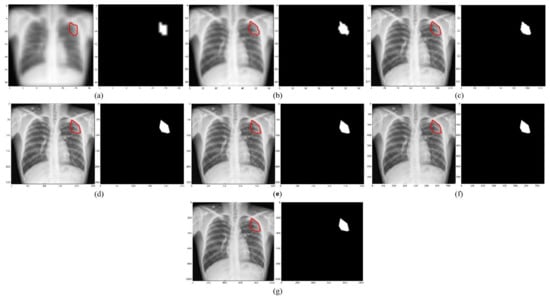

- The 287 CXRs and their associated TB masks were directly down-sampled using bi-cubic interpolation to the aforementioned resolutions. The OpenCV package (ver. 4.5.4) was used in this regard.

- The lung masks were overlaid on the CXRs and their associated TB masks to delineate the lung boundaries. The lung ROI was cropped to the size of a bounding box and also down-sampled to the aforementioned resolutions.